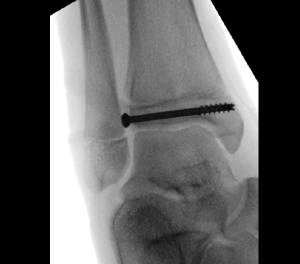

Case 3, Figure 2: 13-year-old female